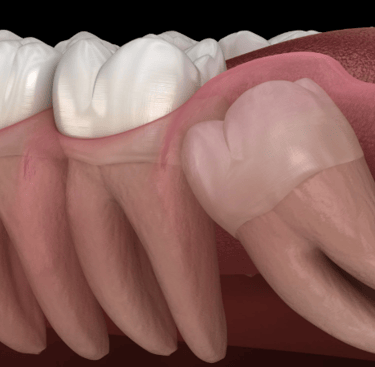

Wisdom Tooth Extraction is a surgical procedure to remove one or more third molars, also known as wisdom teeth. These teeth often grow between ages 17 and 25 and can become impacted,misaligned, or cause crowding and pain. Removing them helps prevent infection, swelling, and damage to other teeth or the jawbone.

Impacted or partially erupted

When wisdom teeth don’t fully emerge, they can trap food and bacteria, causing pain, swelling, and infections in the gums or jaw.

Cysts or jawbone damage

In some cases, impacted teeth can form cysts that damage nearby teeth, nerves, or bone structure,

requiring surgical removal.